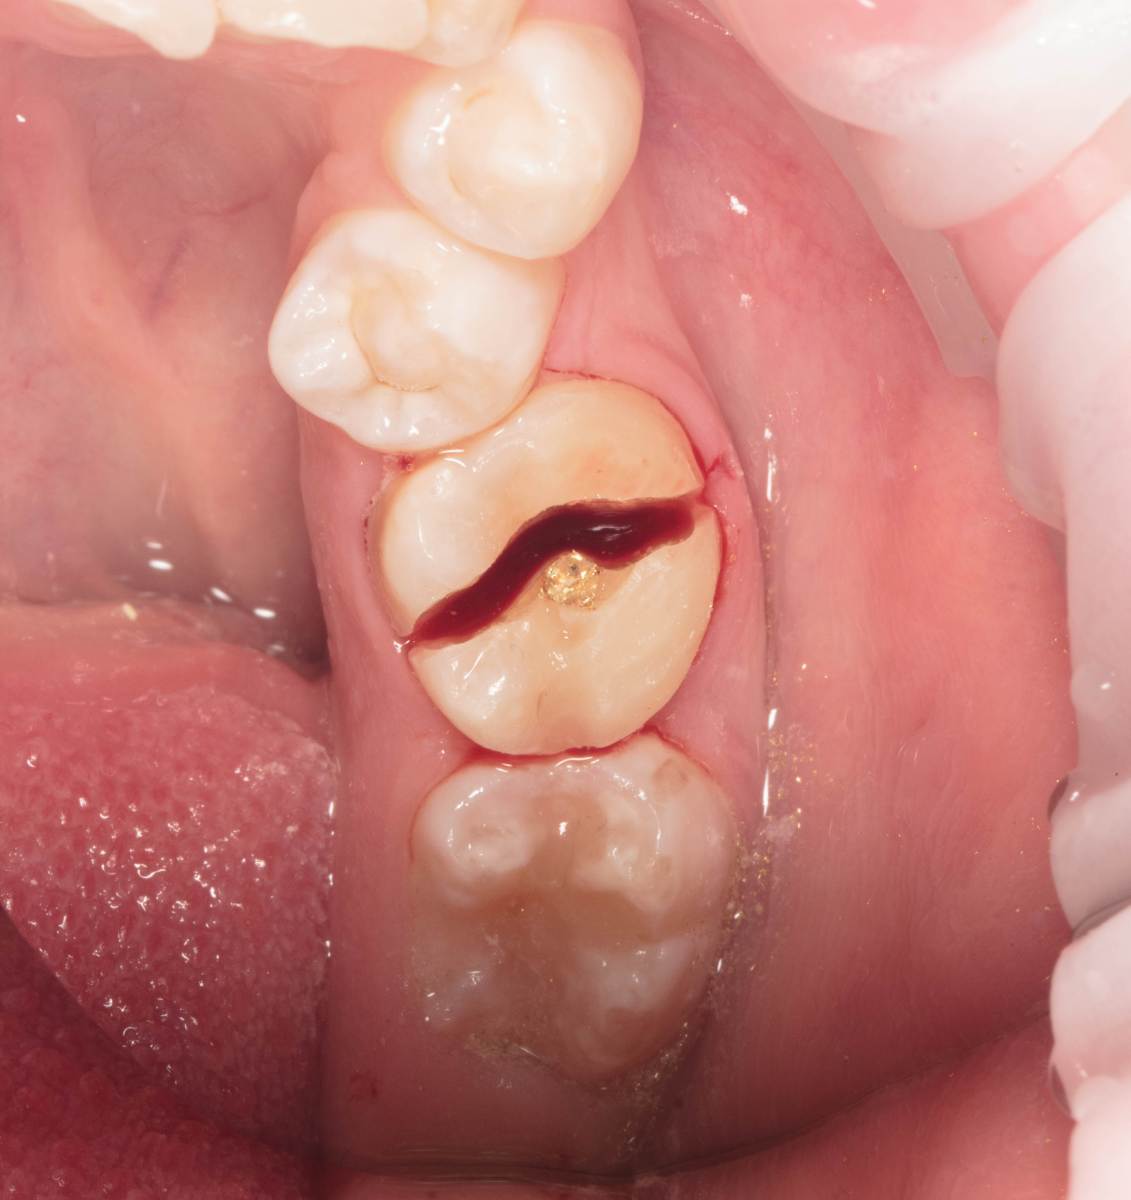

Женька Опубликовано 28 ноября, 2025 Поделиться Опубликовано 28 ноября, 2025 Всем привет, коллеги! 14 лет, терапевты ставят трещину по КТ (снимков до, к сожалению нет, косяк, каюсь). чуть сепарировав зуб и глянув на зуб под отлетевшим куском пломбы трещина "подтвердилась". Кейс на фото. Из интересного - маленький реколл в 1.5 года и спокойное перемещение зуба брекетами! 4 1 2 Ссылка на комментарий

Женька Опубликовано 17 декабря, 2025 Автор Поделиться Опубликовано 17 декабря, 2025 @сирена вот и завтра наступило) прощу прощения, что так долго, всё из головы вылетало на работе посмотреть. Пересадили в конце мая, к ортодонтии подключили в начале сентября ~3.5 месяца прошло с пересадки на тот момент. 1 Ссылка на комментарий